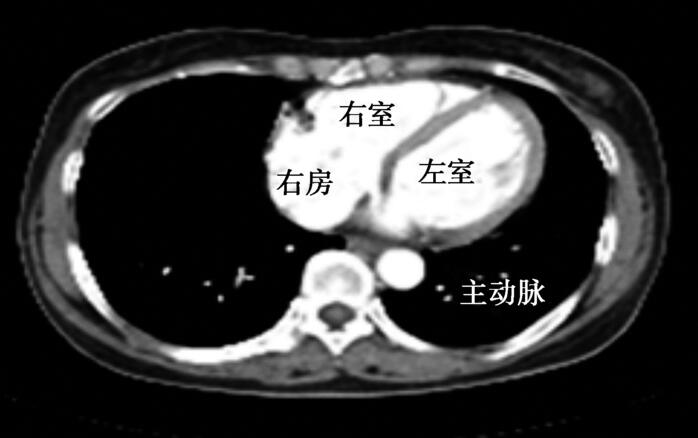

患者4个月前因结核性心包炎于当地医院经抗结核治疗、穿刺引流心包积液后治愈, 2周前因超声心动图提示左心房后肿物再次就诊。此次入院后明确诊断升主动脉假性动脉瘤后行外科手术治疗,术中发现心包严重粘连。胸部CT对心包增厚具有较高的显像分辨率和诊断特异性,可评估心包形状、心脏大血管形态,如腔静脉扩张、左心室后壁纤维化及肥厚等,对可疑缩窄性心包炎具有诊断价值。但是回顾患者影像学资料,胸部CT并未能明确提示心包增厚、粘连(图50-4)。

图50-4 胸部CT未见明显心包增厚、粘连